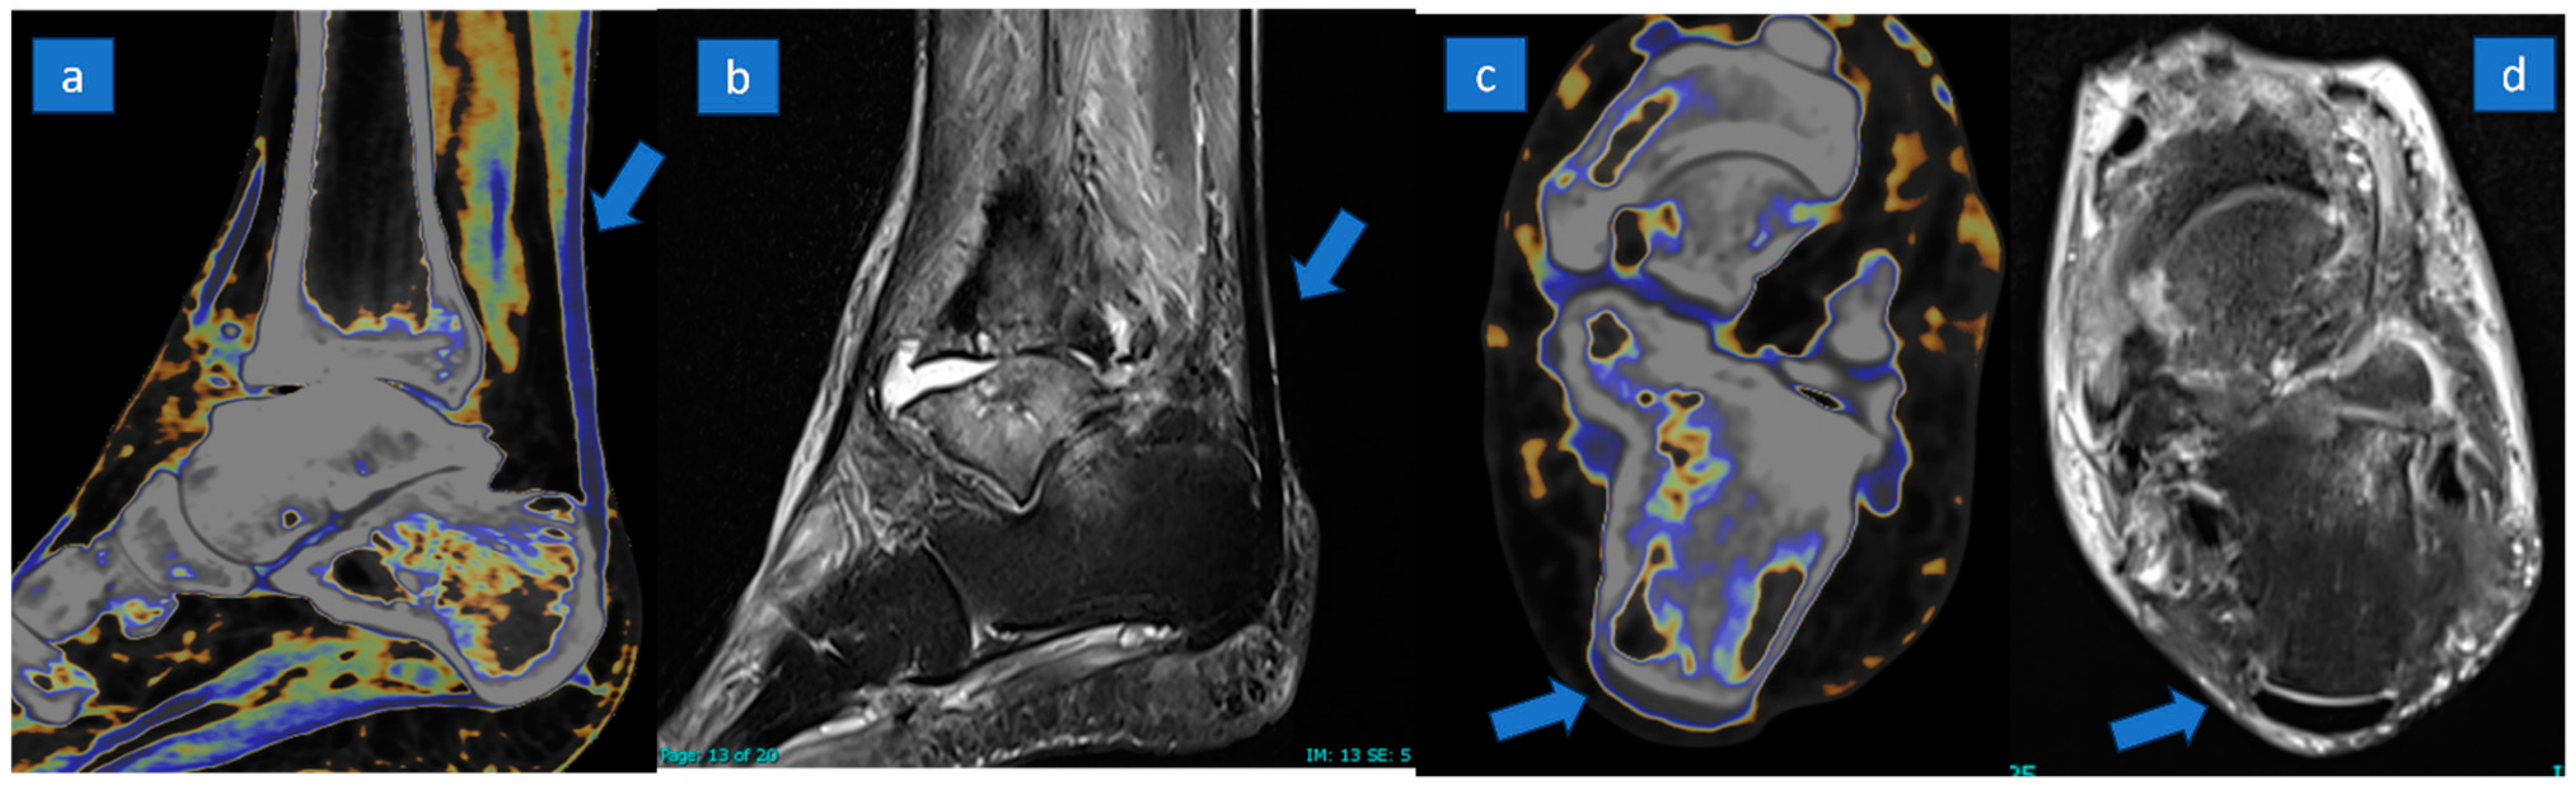

Figure 2.

A 57-year-old male with a painful ankle due to rheumatoid arthritis. Normal tendon (arrow) is coded in blue on sagittal (a) and axial (c) super-imposed color-coded maps. The normal appearance of a tendon (arrow) is confirmed on sagittal (b) and axial (d) PD Fat-saturated MR images.